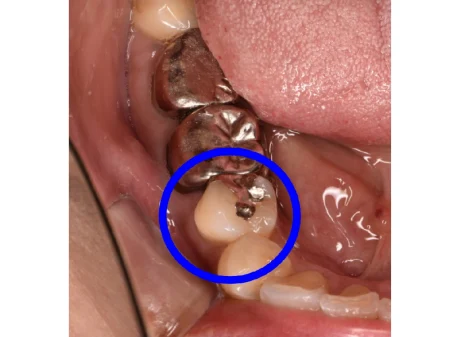

セラミック 2023.0330代女性「歯が痛い」徹底的に虫歯除去した部分を、白くてなじみがいいセラミック素材の詰め物「E-maxインレー」で治療した症例